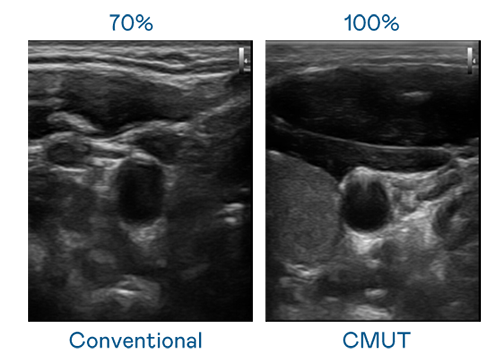

CMUT 技术是一种用电容式微机电元件来产生超音波讯号的技术。与传统 PZT 压电式技术相比,CMUT 频宽增加 30%,更宽频的超音波讯号让影像解析度大幅提升,是实现高影像品质医疗超音波扫描、促进精准医疗发展的关键技术。

超音波影像的解析度高低,首先取决于探头能发出的讯号频宽。OG视讯 CMUT 可提供高清晰的超音波讯号,提供高频宽、高灵敏度、影像纹理细节更高的超音波影像,协助医护人员缩短影像判读时间及利用精准的医疗影像进行诊断。